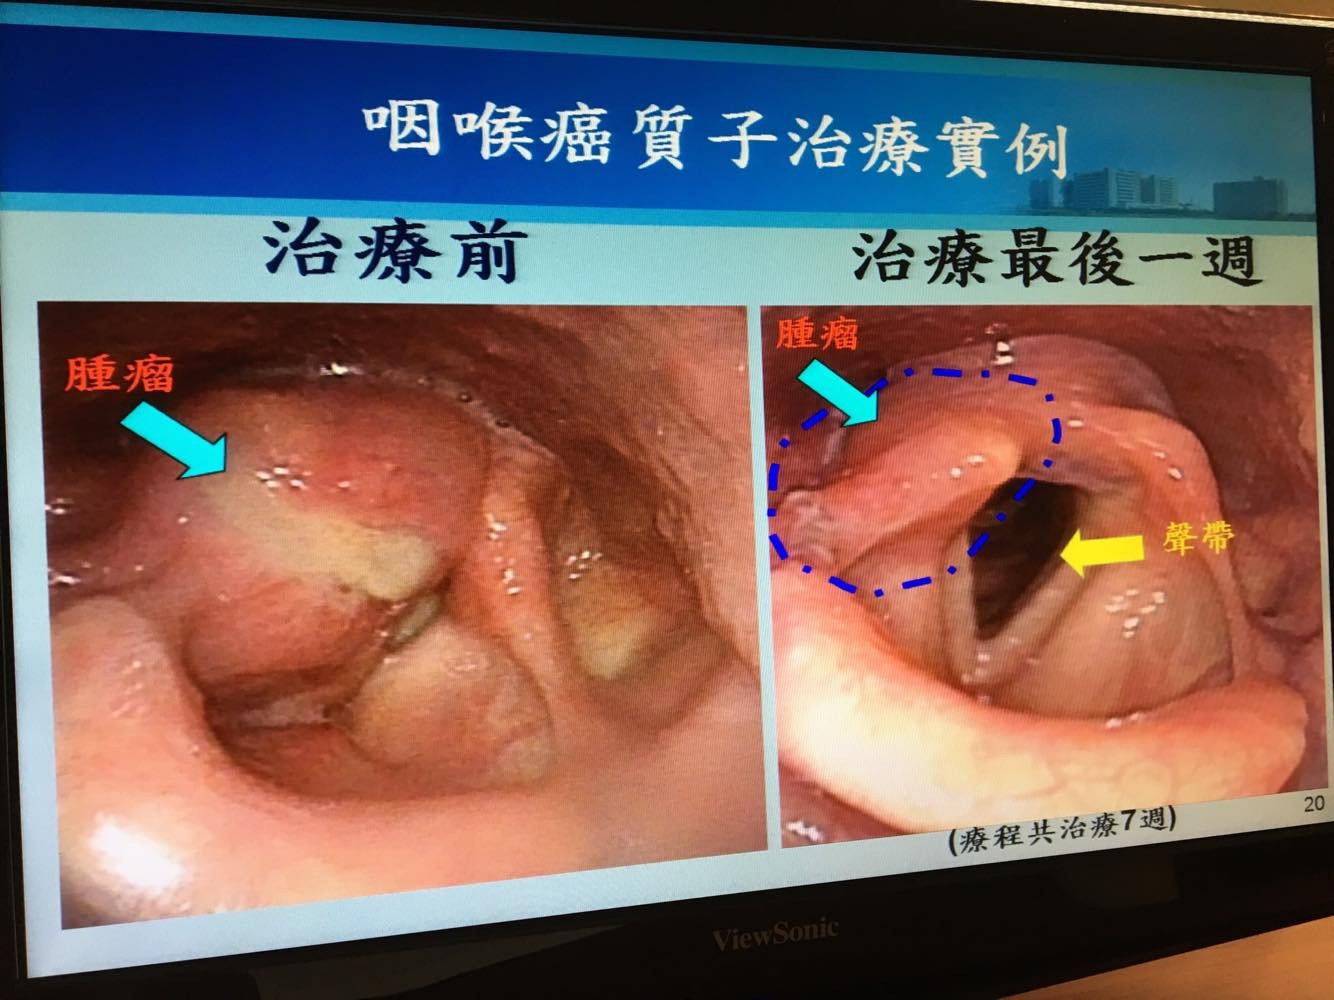

咽喉癌免摘喉 筆尖式質子掃7周腫瘤從團塊 縮成條 Ettoday健康雲